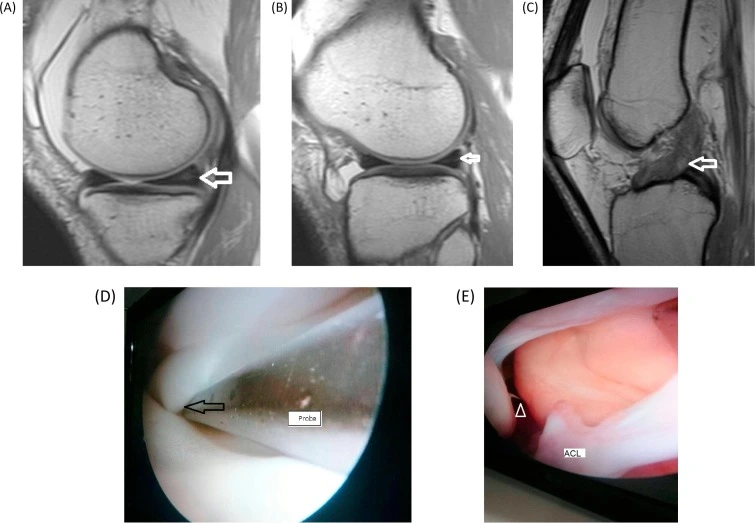

قطع غضروف الركبة من الدرجة الثالثة هو أشد درجات تمزق الغضروف الهلالي، حيث يكون هناك تمزق كامل يصل إلى سطح الغضروف، ويؤدي إلى انفصال جزء منه أو تحركه داخل المفصل.

• يكون التمزق واضحًا في أشعة الرنين المغناطيسي.

عملية غضروف الركبة بالمنظار

عملية غضروف الركبة بالمنظار هي إجراء جراحي بسيط نسبيًا، يتم من خلال فتحات صغيرة في الركبة، باستخدام كاميرا وأدوات دقيقة، وأهداف العملية هي:-

• إزالة الجزء التالف.

• تحسين وظيفة الركبة.

• إصلاح التمزق إن أمكن.